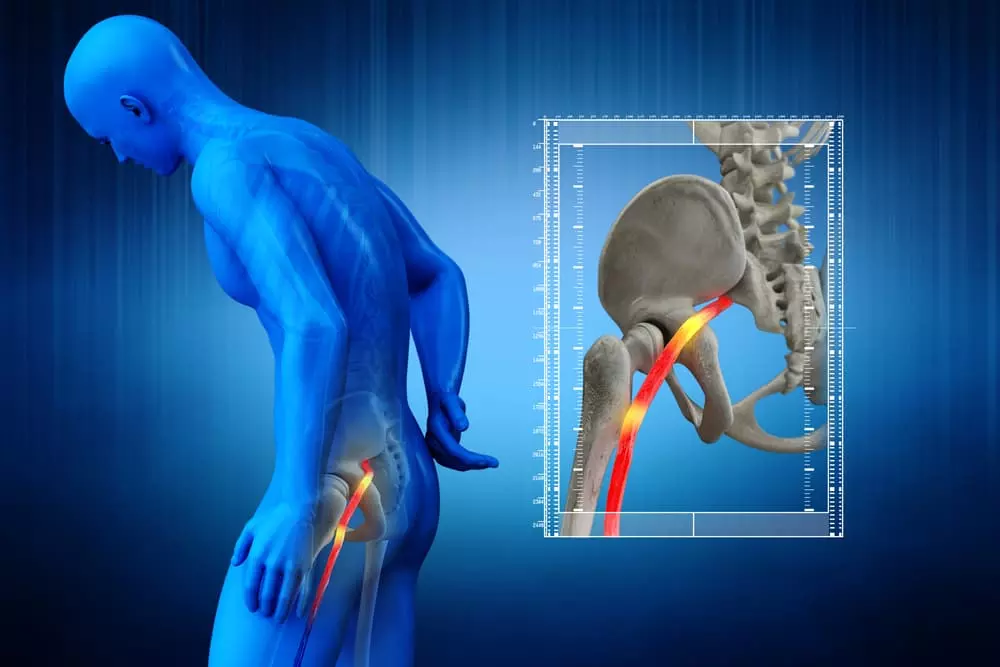

そもそも、坐骨神経とはどんな神経なのか?

坐骨神経は

身体で最も大きく長い神経

坐骨神経は、体内で最も太くて長い神経で、骨盤の後ろからスタートし、お尻の筋肉の間を通り、脚のつま先にまで伸びています。

この神経が、お尻の筋肉や椎間板ヘルニアによって圧迫されると、痛みが生じます。

坐骨神経痛を改善するためには、神経がどの部分で圧迫されているかを正確に見極めることが重要です。